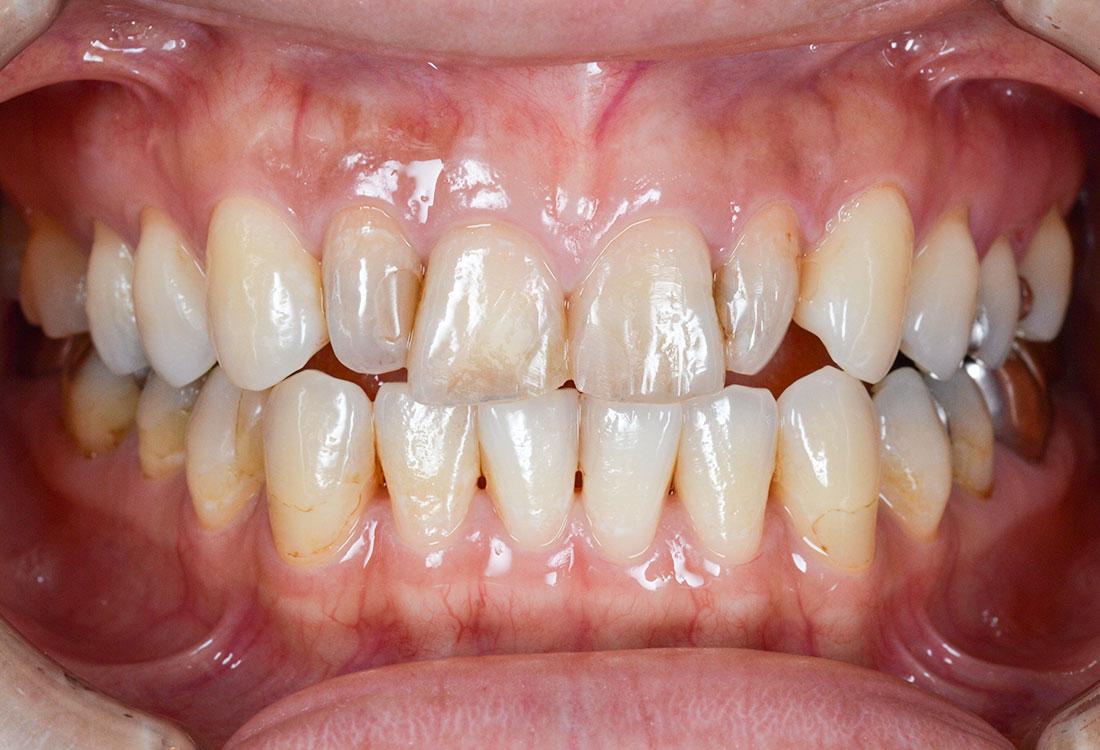

ご相談内容

- 歯の形と見た目が気になる

- 真っ白ではなく色を元の歯の色に合わせてほしい

今回は着色したジルコニアを選択しました。

治療後

着色した被せ物を使うことでとても自然な仕上がりになりました。